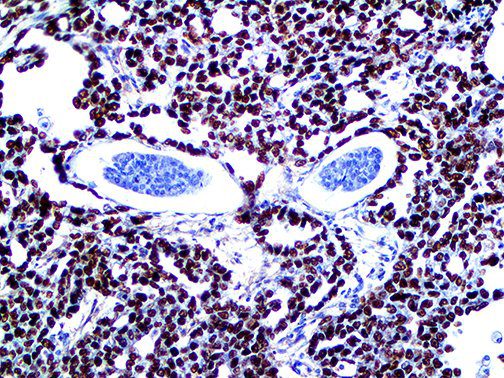

It is the ICU physician who is most likely to witness one of the deadliest manifestations of the abnormal immunological response, the cytokine storm syndrome (CSS). This response is also referred to by some as the cytokine release syndrome (CRS). CSS is characterized by continuous activation and expansion of macrophage and lymphocyte populations, which secrete large amounts of cytokines, causing the cytokine storm. This massive cytokine release is akin to hemophagocytic lymphohistiocytosis (HLH) disease, a syndrome characterized by initial unchecked and persistent activation of cytotoxic T lymphocytes and NK cells.

Clinical and laboratory manifestations of HLH include fever, enlarged liver and/or spleen, neurologic dysfunction, coagulopathy, liver dysfunction, cytopenias (i.e., low levels of erythrocytes, leukocytes, and/or platelets), hypertriglyceridemia, hyperferritinemia, hemophagocytosis, and eventually diminished NK cell activity as the immune system becomes progressively paralyzed. HLH can be familial (primary HLH) or secondary to another disease process (sHLH), such as rheumatic disease, in which it is referred to as macrophage activation syndrome (MAS, characterized by elevated ferritin).